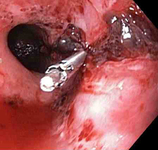

Mallory-Weiss tear

A through-the-scope clip deployed in the center of the lesion (no previous epinephrine was infused in this case)

From the collection of Juan Carlos Munoz, MD, University of Florida